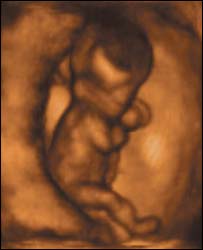

भ्रूण

नई मशीन गर्भस्थ शिशु की हलचलों की तस्वीरें लेता है

प्रोफ़ेसर कैम्पबेल ने जो मशीन तैयार की है वह न केवल त्रि-आयामी तस्वीर लेती है बल्कि उसे उसी समय रिकॉर्ड भी कर लेती है.

उनका कहना है कि उनकी मशीन से बच्चे के विकास के आरंभिक समय की गतिविधियों को देखा जा सकता है.

उन्होंने बीबीसी से कहा, "बच्चे के विकास के दौरान उसके व्यवहार को समझने के लिए यह नया विज्ञान है."

उनका कहना है कि इस मशीन की सहायता से कई जेनेटिक बीमारियों का इलाज किया जा सकेगा.